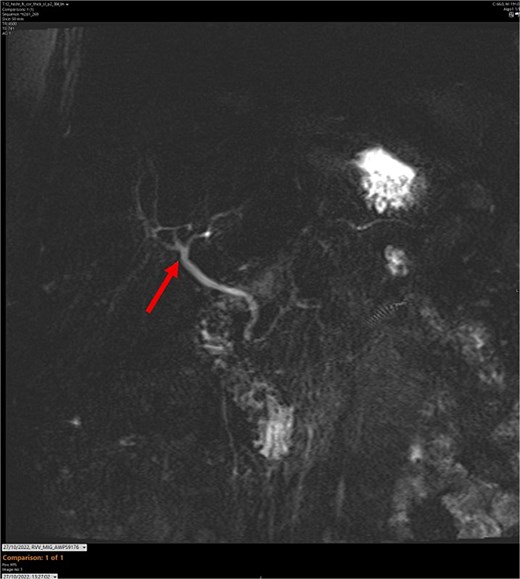

T2-weighted MRCP scan in axial view. The arrow points to where we expect the gallbladder to be seen, but it cannot be visualized on the scan.